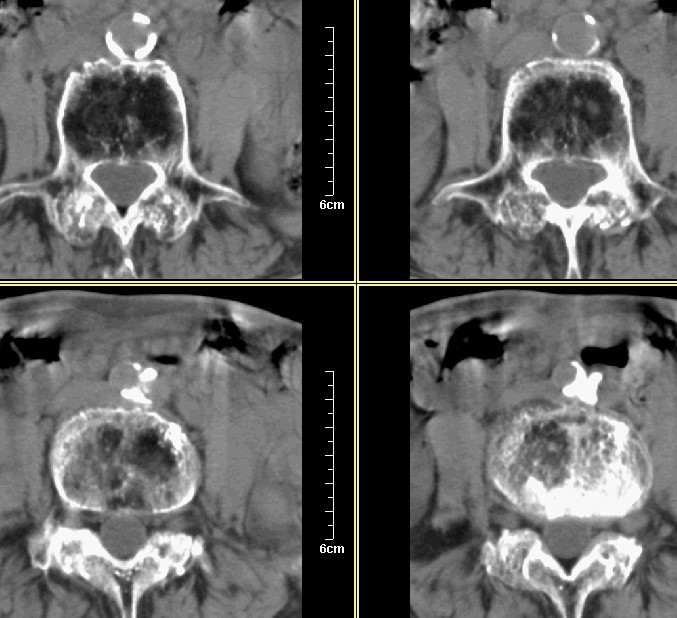

腰1-骶1 间盘及个别椎体扫描

腰3腰4椎体骨质破坏,骨密度低下,骨质疏松,少量骨小梁粗大,紊乱,椎间盘无改变,椎间隙不增宽,椎体无变形,椎旁软组织无肿胀。临床 腰痛明显。考虑:多发淋巴肉芽肿。

骨质疏松症伴退行性骨关节病,患者年龄较大,腹主动脉硬化

腰椎退行性改变,腹主动脉硬化。

多发骨髓瘤?